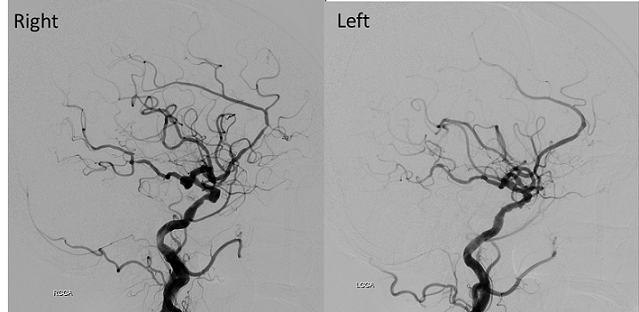

【113-1 醫學(四) 第74題】84歲女性,有高血壓病史,突然頭痛噁心而至急診求診。頭部電腦斷層檢查發現有廣泛蜘蛛網膜下腔出血(subarachnoid hemorrhage, SAH)併腦室內出血;進一步做頭部血管攝影檢查,影像如附圖(右側及左側頸動脈造影),造成她SAH的原因最可能為下列何者?

詳解

破題關鍵

這題的關鍵在於從腦血管攝影(angiography)影像中,精準找出造成蜘蛛網膜下腔出血(SAH)的腦動脈瘤位置。仔細觀察右側頸動脈造影,可以清楚看到一個囊狀突起。